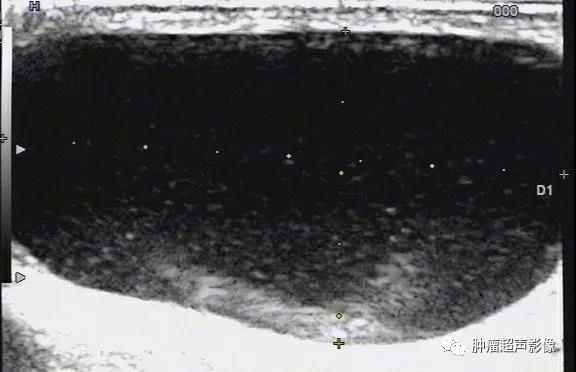

鞘膜积液术后,阴囊见中等回声,未见血流,这是一个发生病变的睾丸吗?

继续扫查可见睾丸(T)被压迫在一边,这其实是一个血性睾丸鞘膜腔积液

穿刺后睾丸鞘膜腔血性积液:充满密集点状回声